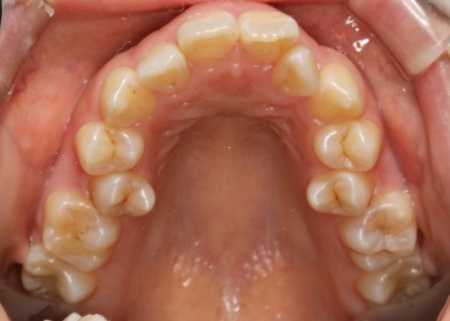

拝見したところ、上下の歯が正しく並ぶためのスペースが足りず、デコボコに生えていました。

とくに、犬歯が正しい歯並びから大きく飛び出した位置に生えており、いわゆる八重歯の状態です。

また、奥歯を噛み合わせた際に上下前歯が噛み合わず隙間ができる開咬(かいこう)も認められました。